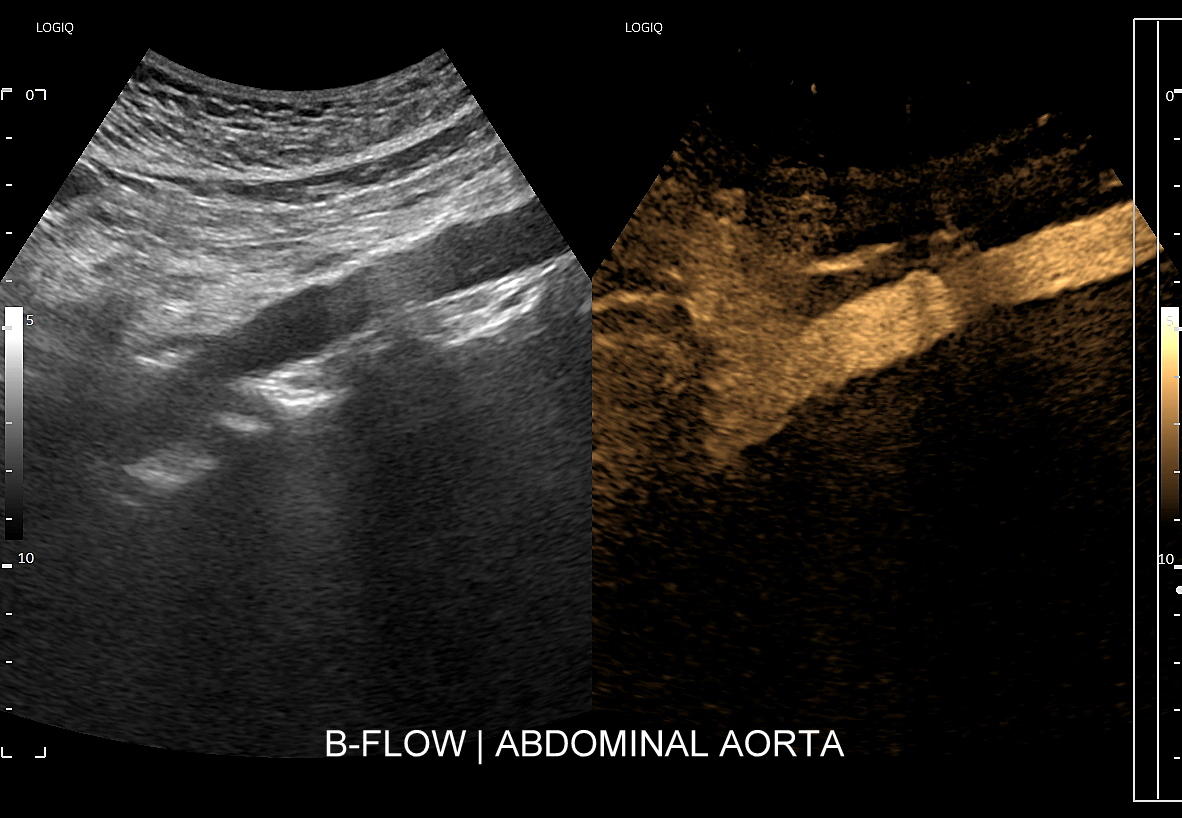

Tryb B-flow wyjątkowo korzystnie sprawdza się także przy badaniu wnętrza dużych i średnich naczyń. Otóż umożliwia on pewne zobrazowanie drożności naczynia, umożliwia wykazanie obecności / lokalizacji naczynia przy niesprzyjających warunkach obrazowania w trybie B, a poza tym uzyskiwane w omawianym trybie obrazy zarysów błony wewnętrznej naczyń (np. tętniczych blaszek miażdżycowych, skrzeplin przyściennych, zmian w przebiegu dysplazji włóknisto-mięśniowej, czy zapaleń tętnic) charakteryzują się wysoką rozdzielczością i kontrastowością. Skany dużych naczyń w trybie B-flow przypominają wręcz te uzyskiwane w klasycznej angiografii opartej o promieniowanie rentgenowskie. B-flow wykorzystywany może być praktycznie i rutynowo do obrazowania naczyń szyi i kończyn, naczyń wątroby, naczyń trzewnych, nerkowych oraz dużych naczyń brzusznych.